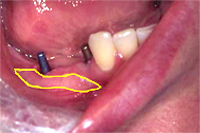

Zwei Implantate, hier bereits eingeheilt und mit den eingeschraubten Aufbauten versehen, werden in einer auf den Millimeter genauen Distanz gesetzt, um eine dreigliedrige Brücke aus Metallkeramik aufzunehmen (Abb. 1) und so die Lücke zu schliessen, die durch das Ziehen des Zahnes entstanden ist. Dann wird die Metallkeramikbrücke zementiert (Abb. 2).

- Vorgängig der Implantation habe ich in dem zahnlosen Kieferabschnitt ein freies Gingivatransplantat verpflanzt (Abb. 1, 2, gelbe Umrandung) (siehe Kap. Mukogingivalchirurgie), um für die Implantatpfosten optimale Zahnfleischbedingungen zu erhalten.